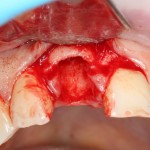

Все начинается с удаления зуба:

Обратите внимание на состояние вестибулярной стенки лунки. В проекции верхушек корней вы можете увидеть костный дефект, вызванный длительным воспалительным процессом (собственно, почему этот зуб пришлось удалять). В этом случае, вестибулярная стенка лунки неизбежно лизируется после удаления зуба, а это приведет не только к проблемам в эстетике, но и осложнит последующий уход за протетической конструкцией. Поэтому в данном случае мы должны продумать, в том числе, аугментацию лунки. И порядок действий здесь несколько иной, нежели в предыдущем случае.

Устанавливается имплантат Astratech (Dentsply Implants):